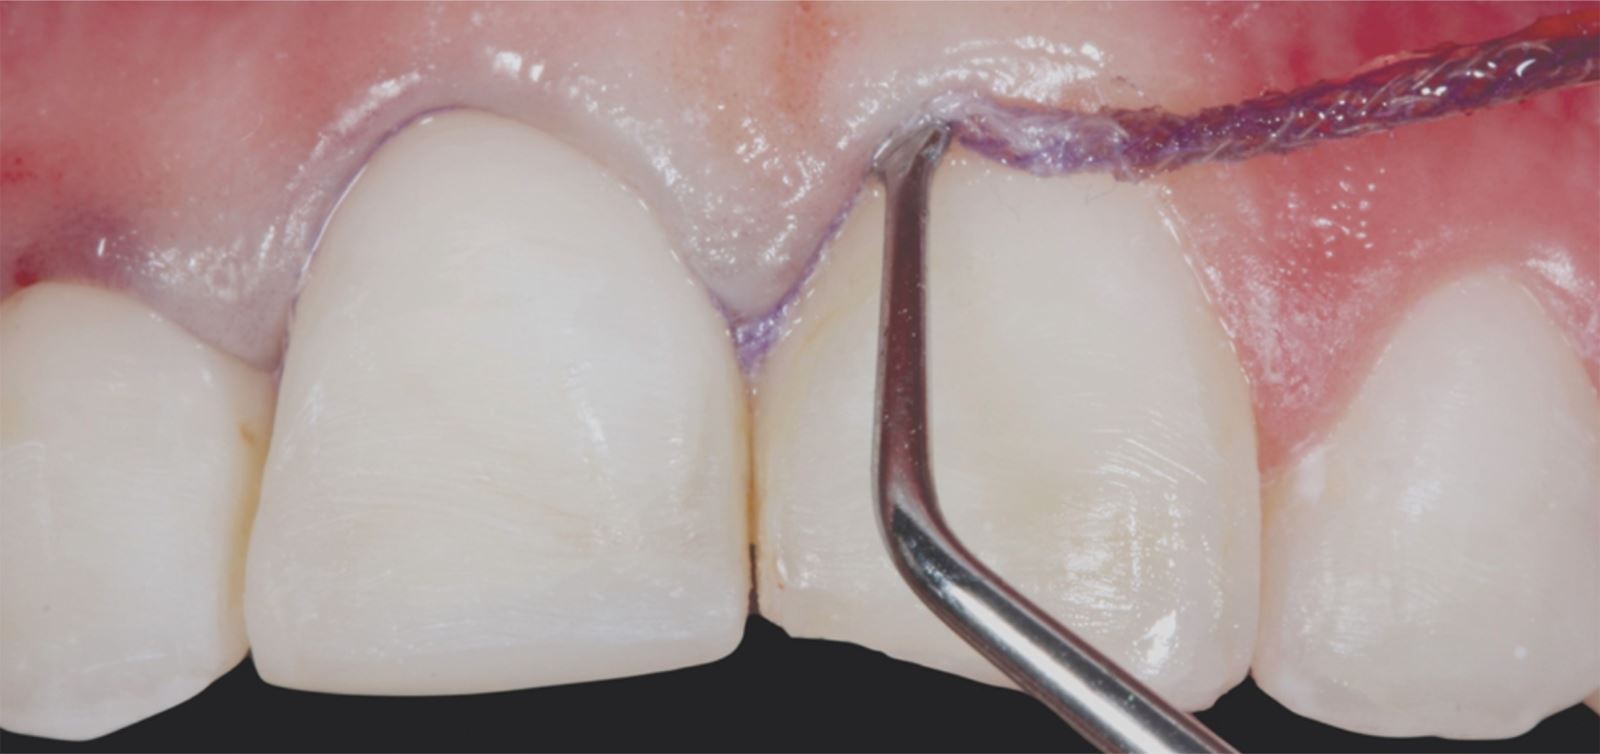

Príprava sulku:

Do gingiválneho sulku boli vložené pletené retrakčné vlákna Ultrapak™ veľkosti #0 na prípravu na leptanie.

Leptanie nepreparovanej skloviny:

Nepreparovaná sklovina bola leptaná 35% kyselinou fosforečnou Ultra-Etch po dobu 30 sekúnd.

Aplikácia a stenčenie adhezíva:

Adhezívum Peak Universal Bond bolo aplikované a stenčené vzduchom so súčasným odsávaním.

Cementácia:

Fazety boli cementované pomocou živicového cementu PermaShade™ LC v odtieni Translucent (nie je dostupný v Európe).